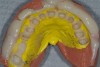

Figure 5  Laboratory alteration of the gingival contours in diagnostic wax-up.

Figure 5